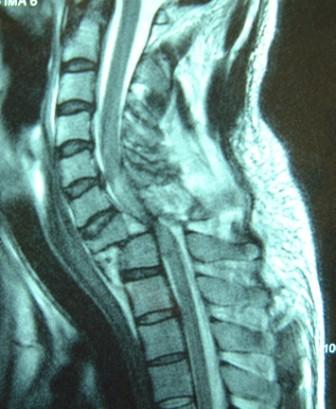

La frattura di una o più vertebre o la frattura di una o più costole con perforazione di uno o entrambi i polmoni, sempre che non ci sia un'annessa compressione da schiacciamento.

Cosa usiamo per proteggere quella zona? Il paraschiena (se ce l'abbiamo) e la tuta o la giacca in pelle.

Ma ad esser sinceri, cosa possono fare questi strati di pseudo-cotenna in più se andiamo a sbattere a velocità oltre i 70 km/h contro ad un palo, ad una macchina o ad un cartello autostradale? Ben poco.